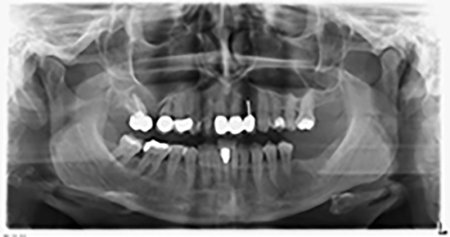

La paciente de 59 años presentaba una periodontitis avanzada, describía una desagradable sensación y un mal gusto proveniente del primer cuadrante. La evaluación clínica mostró en general marcadas profundidades de bolsa y una degeneración ósea muy avanzada en las regiones 16 y 14. El estudio radiológico corroboró estos resultados (figura 1). Las piezas dentales 16 y 14 no podían conservarse.

Unos seis meses después de la extracción de las piezas 16 y 14 se realizó una tomografía digital de volúmenes (DVT, Planmeca) para realizar una planificación adecuada y reducir los riesgos al mínimo. En este punto se constató que el hueso no se había regenerado en la cantidad deseada (figuras 2 a 7).